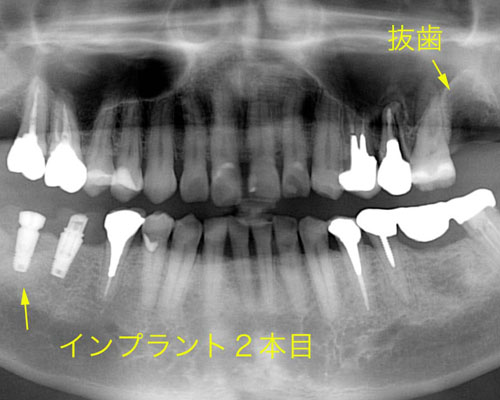

2本目のインプラント

右側に1本インプラントの仮歯が入ったので、代わりに左上を1本抜かせてもらい、右下に2本目のインプラントを入れました。この時点では、まだ左側を中心食事をされていたそうです。ちょっと一安心ですね。